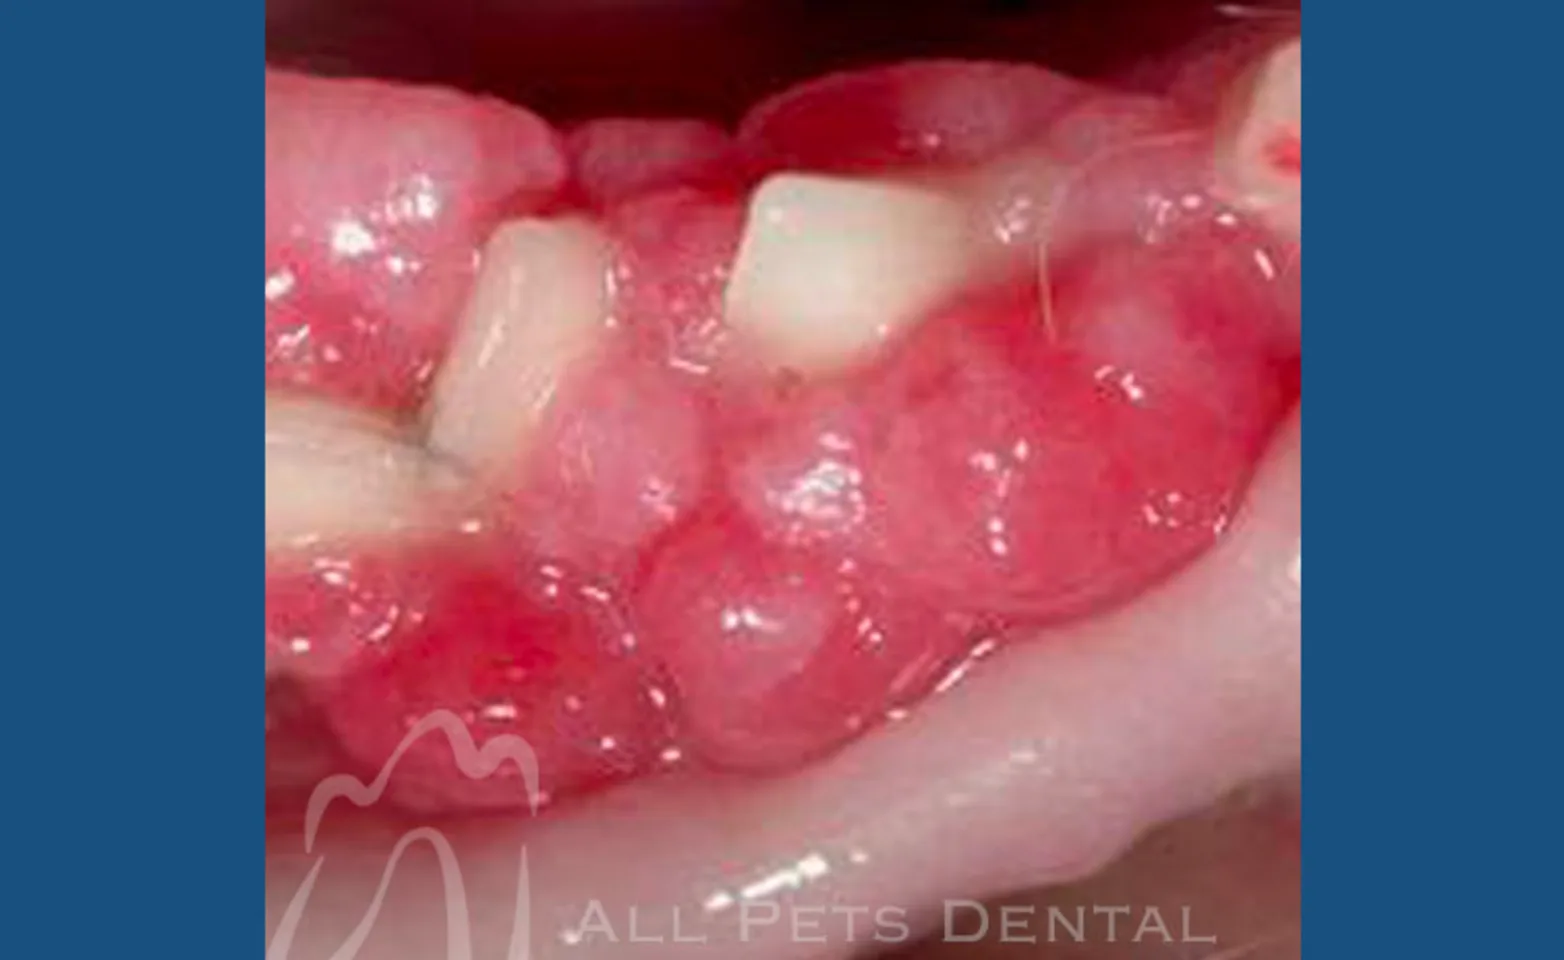

Peripheral Odontogenic Fibroma

Peripheral odontogenic fibromas include fibromatous and ossifying epulides. Epulis (plural=epulides) is a general term referring to a gingival mass of any type. This term has been adapted in veterinary nomenclature to refer to tumors arising from epithelial remnants within the periodontal ligament. The ossifying type is distinguished from the fibromatous type by containing varying amounts of bone, osteoid, dentinoid, or cementum-like tissue. Treatment of choice is removal of the mass and often the underlying tooth to prevent further spread.